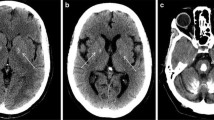

Primary familial brain calcification (PFBC), formerly known as Fahr’s disease or idiopathic basal ganglia calcification, is an inherited and intractable disorder mainly characterized by progressive bilateral calcification distributed in the basal ganglia region and/or other areas of the brain [7]. PFBC can serve as an ideal model in which to study the pathogenesis and potential prevention and treatment of brain calcification. PFBC can result in a variety of clinical symptoms, ranging from occasional migraines to serious symptoms including motor disorders (parkinsonism, tremor, and dystonia), cognitive disorders (memory impairment, executive dysfunction symptoms, and mental retardation), and neurological disorders (depression, affective disorder, and insanity), but nearly one-third of the carriers of causative gene mutation are asymptomatic [3, 8, 9]. Due to the high degree of clinical heterogeneity, the clinical symptoms are not suitable criteria for a diagnosis of PFBC. In contrast, the clinical diagnosis mainly relies on brain calcification identified by computed tomography (CT). The most typical feature in the neuroimages of PFBC patients is symmetrical bilateral calcification in the basal ganglia, thalamus, frontal cortex, or cerebellum. However, the levels of calcium (Ca), phosphorus (P), alkaline phosphatase, parathyroid hormone, and other serum biochemical indicators are normal in PFBC patients [3, 10, 11]. The overall prevalence of PFBC is estimated to be 0.21%–0.66% [12, 13].

It has been >170 years since the initial report of a case of bilateral basal ganglia calcification by Delacour in 1850 [14]. The genetic etiology of PFBC was largely unknown before the identification of SLC20A2 as the first associated gene in 2012 by Prof. Jing-Yu Liu’s lab [11]. A few pathological studies found that the main component of brain calcification is hydroxyapatite [15, 16]. Calcification particles mainly occur in adventitial vessel cells and sometimes in glial cells, as observed by transmission electron microscopy. Some spherical and hemispherical calcium deposits have been located in the vascular adventitia and connected to the filamentous processes of surrounding cells, as observed by scanning electron microscopy [17]. Furthermore, in some PFBC cases, large spherical calcification particles, mainly calcium phosphate, have been reported to be attached to the capillary wall and located in the media of some large arteries, and reactive astrocytes and microglia have been found to accumulate around the calcification sites [18, 19]. A few neurofibrillary tangles and dystrophic neurites in the medial temporal lobe, rarely spreading senile plaques, and a few amyloid deposits in vascular walls have been detected by silver staining and immunohistochemical staining [20]. Overall, these studies demonstrate that brain calcifications are mostly associated with blood vessels and sometimes involve neurons or glial cells, but the calcification process is still largely unknown.